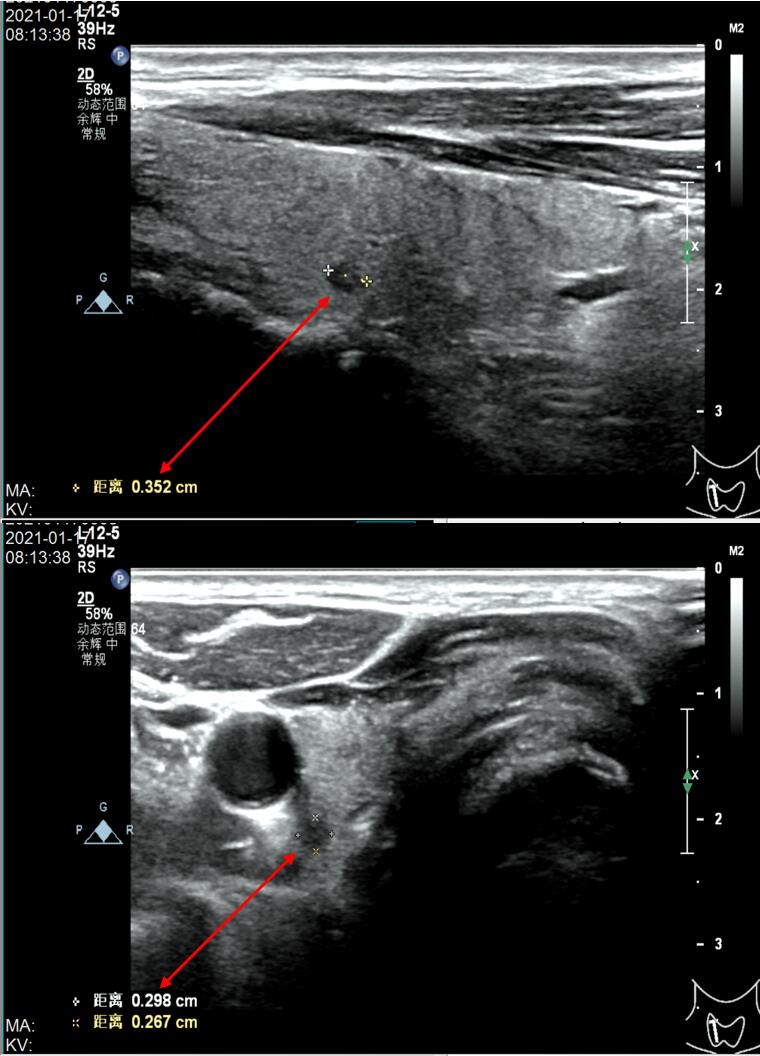

67岁的梁伯伯,1年前因“甲状腺左叶乳头状癌”行外科手术切除甲状腺左叶全部与右叶大部分甲状腺组织。术后梁伯伯以为手术切除后就完全好了而没有按时复查。现在术后1年多了才来医院检查甲状腺超声,但很不幸,甲状腺超声发现梁伯伯仅剩一点点的甲状腺右残叶又长了一个芝麻粒大小结节(0.352cm*0.298cm*0.267cm),还是4类,如下图。

超声对诊断甲状腺结节的良、恶性具有很高的价值,优秀的超声医生对甲状腺结节良、恶性鉴别的准确性可达90%。但是超声检查对操作者的依赖性非常严重,对同一结节,不同超声医生可能会做出截然不同的诊断。我院超声检查诊断梁伯伯的甲状腺右侧残叶结节为4类,而梁伯伯1年前确诊甲状腺左叶乳头状癌并外科手术切除。我院内分泌科、普外科及介入科会诊后,根据国际与国内权威标准(凡直径>1cm的甲状腺结节,均可考虑超声引导下甲状腺结节细针穿刺抽吸细胞学检查;直径<1cm的甲状腺结节如伴有可疑超声征象或其他危险因素,也可考虑超声引导下甲状腺结节细针穿刺抽吸细胞学检查),则建议梁伯伯在介入科用超声引导下行细针穿刺抽吸细胞学检查明确结节是良性还是恶性。虽然梁伯伯的甲状腺右侧残叶结节只有芝麻粒大小(0.352cm*0.298cm*0.267cm),而且微小结节位于甲状腺的深面背侧,但是介入科开展甲状腺结节细针穿刺活检已经很多年,积累了丰富的临床经验,还是比较有信心能成功穿刺活检的。最后不负众望,介入科用超声引导下作甲状腺结节细针穿刺活检后将细胞标本送病理科沉渣包埋制片,我院病理科医生的细胞学病理诊断经验非常丰富,在送检的细胞学标本中找到了甲状腺乳头状癌细胞即可作出甲状腺乳头状癌的病理细胞学诊断(如下图)。